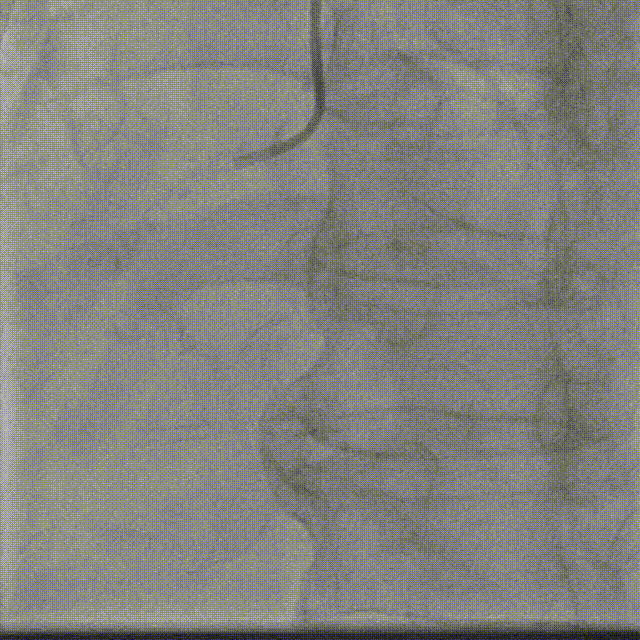

旋磨头

在旋磨中可实现:

完美兼容1.75mm及更小的旋磨头

(1.75mm旋磨头通过尺寸要求0.073")